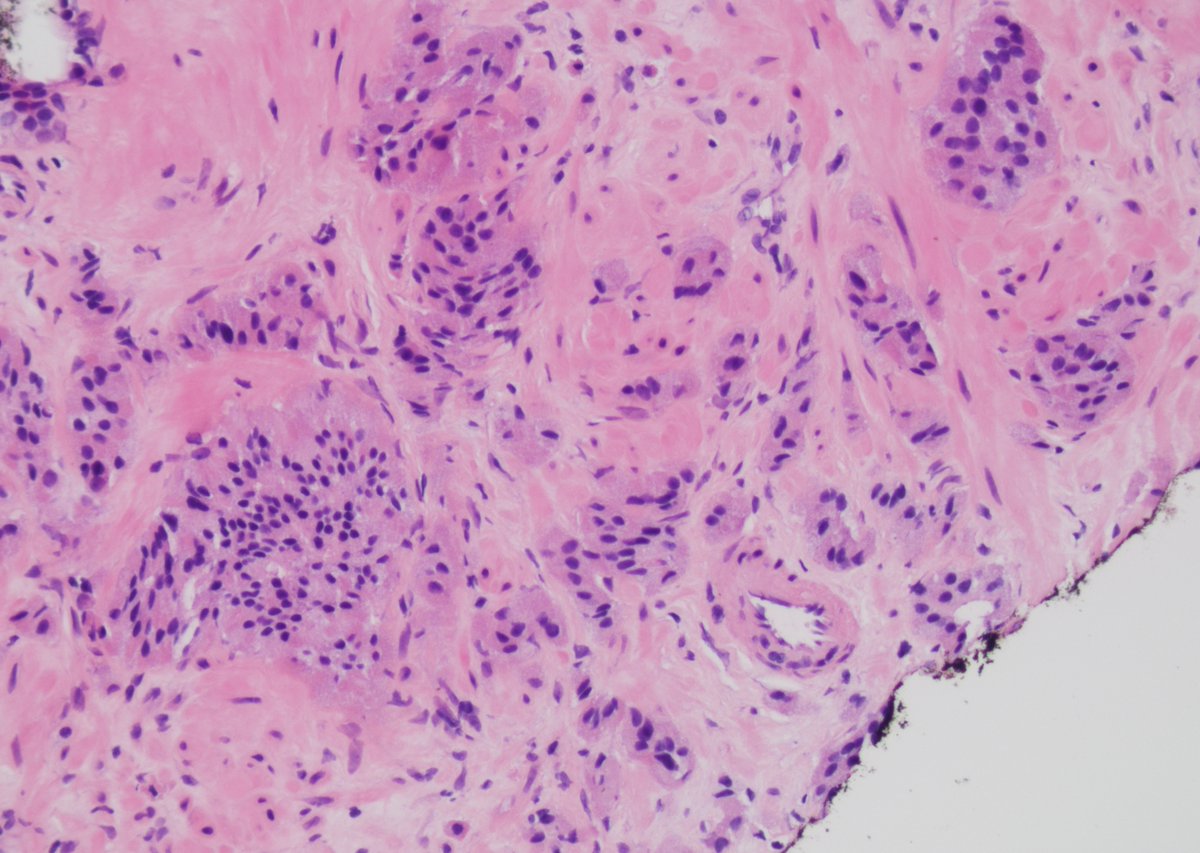

Prostate Cell News focuses on recent scientific journal articles covering prostate cell biology, cancer research, and related disease models.